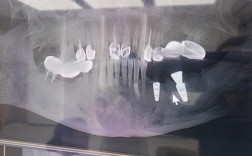

种植牙前必看!骨量CT测量究竟有多重要?附详细解读与流程“想做种植牙,医生却让我先拍个CT,说是测骨量?骨量不足是不是就不能种了?”“别人种牙几个月就搞定,我为什么要多一步CT检查?是不是套路?”在种植牙咨询中,类似的问题屡见不鲜,很多患者...